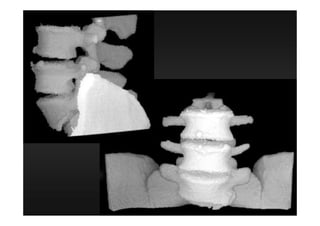

Procedimentos Especiais 3 D MIP(angio) MPR (2 D) 4 D Todas as aquisições devem ter espessura finas e incremento de 50 a 70 % da espessura (quanto mais informação, mais fidedigna será a reconstrução multiplanar)

figura